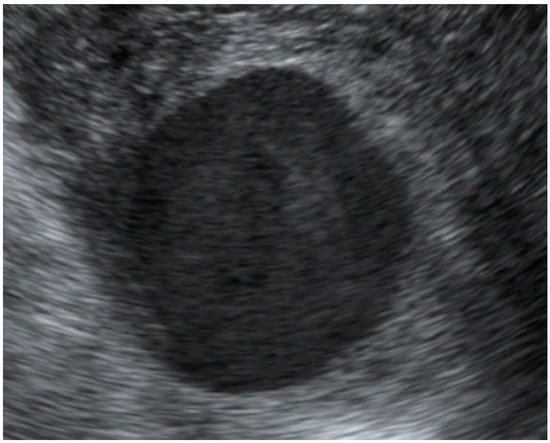

An Unruptured True Aneurysm of the Uterine Artery during Pregnancy